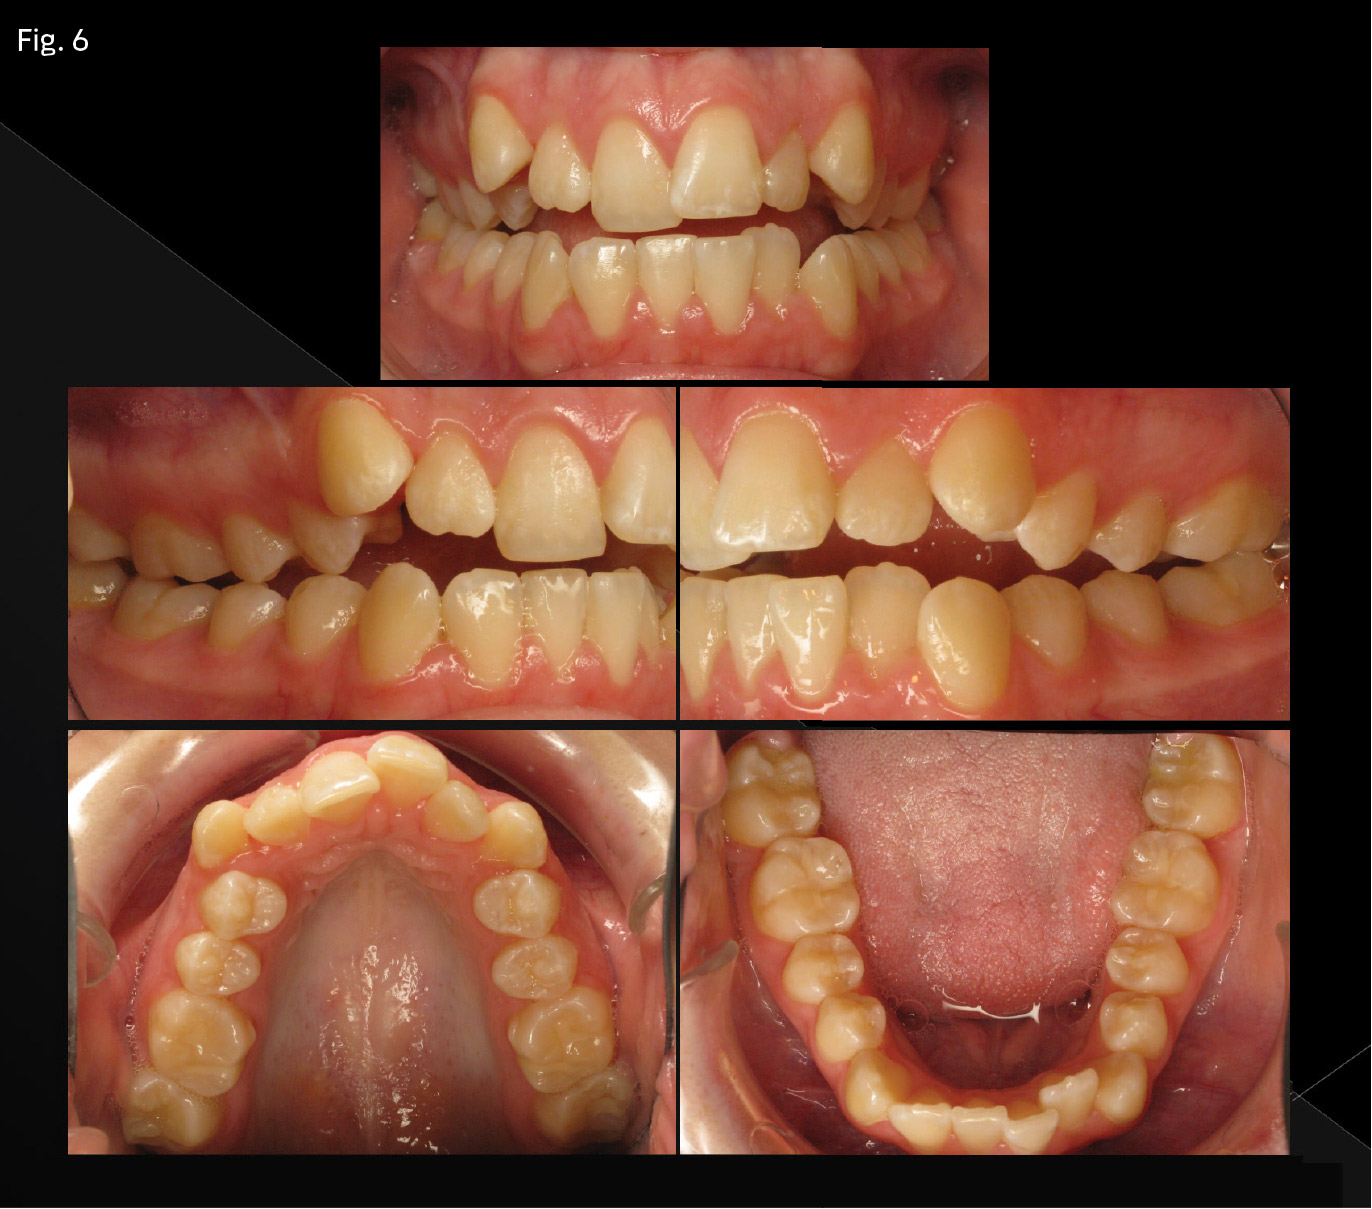

Patient (Figs. 5 and 6) presented with the following chief complaint: “I want my front teeth to come together when my teeth are straight.”

Anteroposterior: Molar canine relationships are a half-step Class II. The overjet measurement is 4mm, measured at the left central incisor. The skeletal relationships are mildly Class II. The mandible is posterior divergent, and the lower anterior face height is larger than average.

Vertical: An anterior open bite of 5mm is measured at the right maxillary lateral incisor. The maxilla shows posterior vertical maxillary excess—upon smiling, there is 5mm of gingival display.

Perimeter: Moderate crowding is present in both arches.

Transverse: A constricted maxillary arch form relative to the lower arch is present, resulting in buccal-cusp-to-buccal-cusp relationships extending from the second molars to the first bicuspids on both sides, a bilateral posterior crossbite tendency. However, the patient does have adequate lip competence at rest.